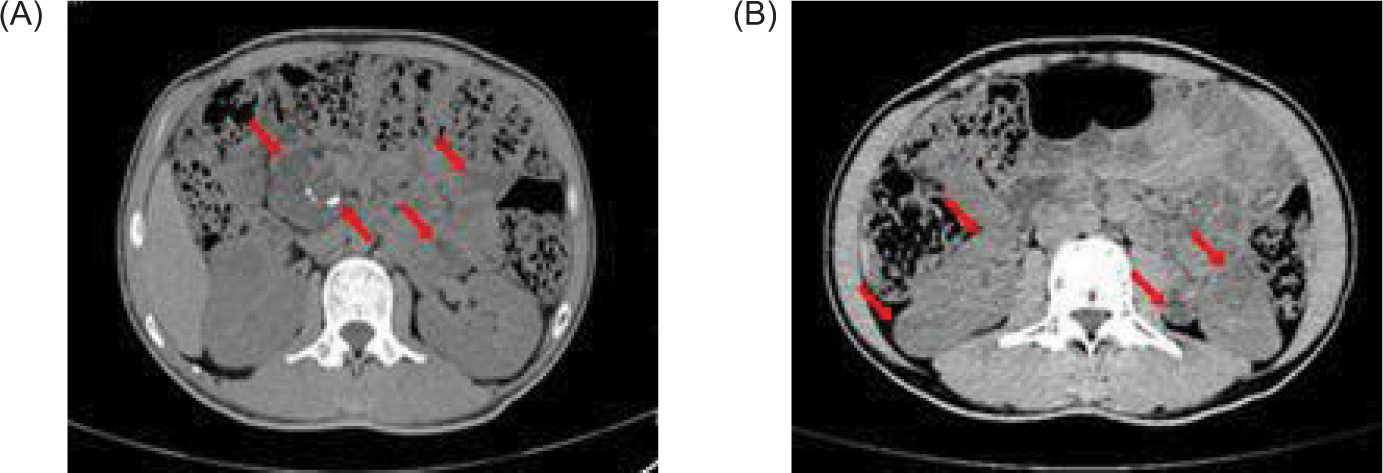

Full abdominal CT and lung CT revealed a high-risk pulmonary nodule in the right lower lobe (Figure 4), pancreatic enlargement with multiple cystic lesions, and multiple ill-defined low-density lesions in both kidneys (Figure 5).

Figure 4: Lung CAT (CT) shows a ground glass nodule (12×9 mm) in the posterior basal segment of the right lower lobe (IM51), with signs of pleural depression (red arrow).

Figure 5: Full abdominal CAT (CT) scan shows pancreatic enlargement with (A) multiple cystic foci and scattered calcification in the pancreas (red arrow), and (B) multiple low-density nodules in the kidney (red arrow).